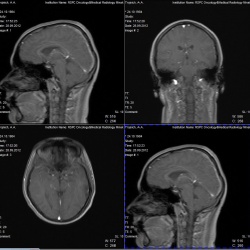

Молодой парень, 27 лет. Случайно прошел МРТ головного мозга. Иногда беспокоят головные боли, других жалоб нет. Поставлено два различных диагноза радиологом и нейрохирургом. Пожалуйста, очень нужна...